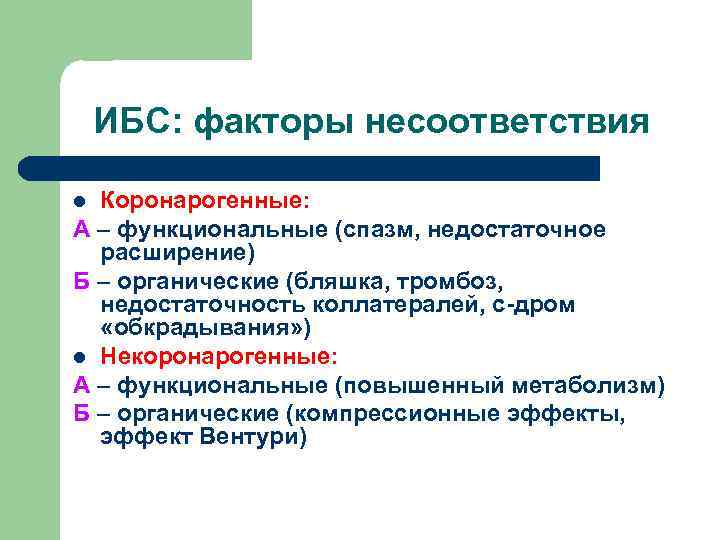

ИБС: факторы несоответствия Коронарогенные: А – функциональные (спазм, недостаточное расширение) Б – органические (бляшка, тромбоз, недостаточность коллатералей, с-дром «обкрадывания» ) l Некоронарогенные: А – функциональные (повышенный метаболизм) Б – органические (компрессионные эффекты, эффект Вентури) l